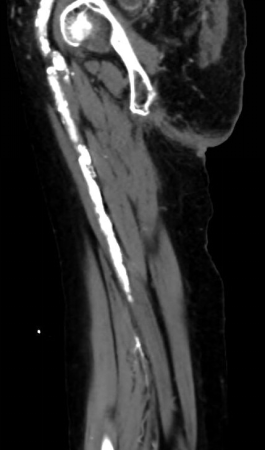

辅助检查:股浅动脉中上段节段性狭窄,下段闭塞,胫前、胫后动脉闭塞,钙化严重。

1. 术前造影:

2. 经鞘置入椎管、CXI、V18导丝正向开通股浅动脉下段,导丝通过,导管无法跟进,经皮穿刺钙化灶,导管跟进造影发现位于内膜下。

3. 经皮穿刺胫前动脉上段,置入新V18导丝,跟进CXI,与正向的椎管双向会师,建立导丝通路,予以3.0球囊预扩张。